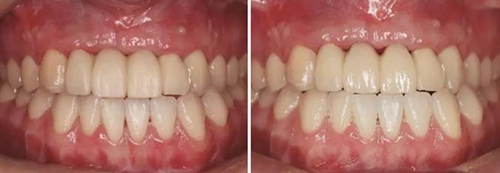

(4)2015年3月—2015年12月:早期修復(fù)伴軟組織誘導(dǎo)成形對(duì)患者制取開窗印模后,使用橋用金屬臨時(shí)基臺(tái),制作聚甲基丙烯酸甲酯(PMMA,登士柏公司,德國(guó))經(jīng)CAD/CAM切削的臨時(shí)修復(fù)橋體,戴入臨時(shí)修復(fù)體對(duì)牙齦軟組織進(jìn)行誘導(dǎo)成形,采用動(dòng)態(tài)加壓技術(shù),最初緩慢戴入臨時(shí)修復(fù)體,撐開牙齦軟組織袖口,擠壓粘膜,粘膜受到擠壓后缺血變白,10min內(nèi)可恢復(fù)為粉紅色。臨時(shí)修復(fù)體為縱向螺絲固位,便于拆卸調(diào)改形態(tài),囑患者勿用臨時(shí)修復(fù)體咬物,注意口腔衛(wèi)生,用牙線或沖牙器等將種植體周圍清潔干凈,每月進(jìn)行復(fù)查,不斷調(diào)改臨時(shí)冠的穿齦形態(tài),讓出軟組織生長(zhǎng)空間,直至誘導(dǎo)牙齦形成類似于天然牙的穿齦袖口形態(tài)。其中在早期修復(fù)3月時(shí),通過打開修復(fù)體間的三角間隙,以讓出齦乳頭生長(zhǎng)的空間;在早期修復(fù)7月時(shí)對(duì)22位點(diǎn)唇側(cè)牙齦根方的軟組織增生物進(jìn)行刮除并縫合,同時(shí)將修復(fù)體的橋體部位調(diào)磨成卵圓形的蓋嵴部并高度拋光,以獲得良好的橋體部軟組織形態(tài),形成健康、連續(xù)且協(xié)調(diào)的軟組織輪廓。

(5)2016年1月:軟組織塑形10個(gè)月后,牙齦形態(tài)穩(wěn)定,制取終印模行個(gè)性化全瓷修復(fù)。

圖21 早期修復(fù)3月 圖22 早期修復(fù)3月打開三角間隙

圖23 早期修復(fù)4月 圖24 早期修復(fù)7月切除軟組織增生后

圖25 早期修復(fù)7月調(diào)改橋體部形態(tài)為卵圓形并高度拋光 圖26 早期修復(fù)8月

圖27 早期修復(fù)8月調(diào)改后 圖28 早期修復(fù)10月